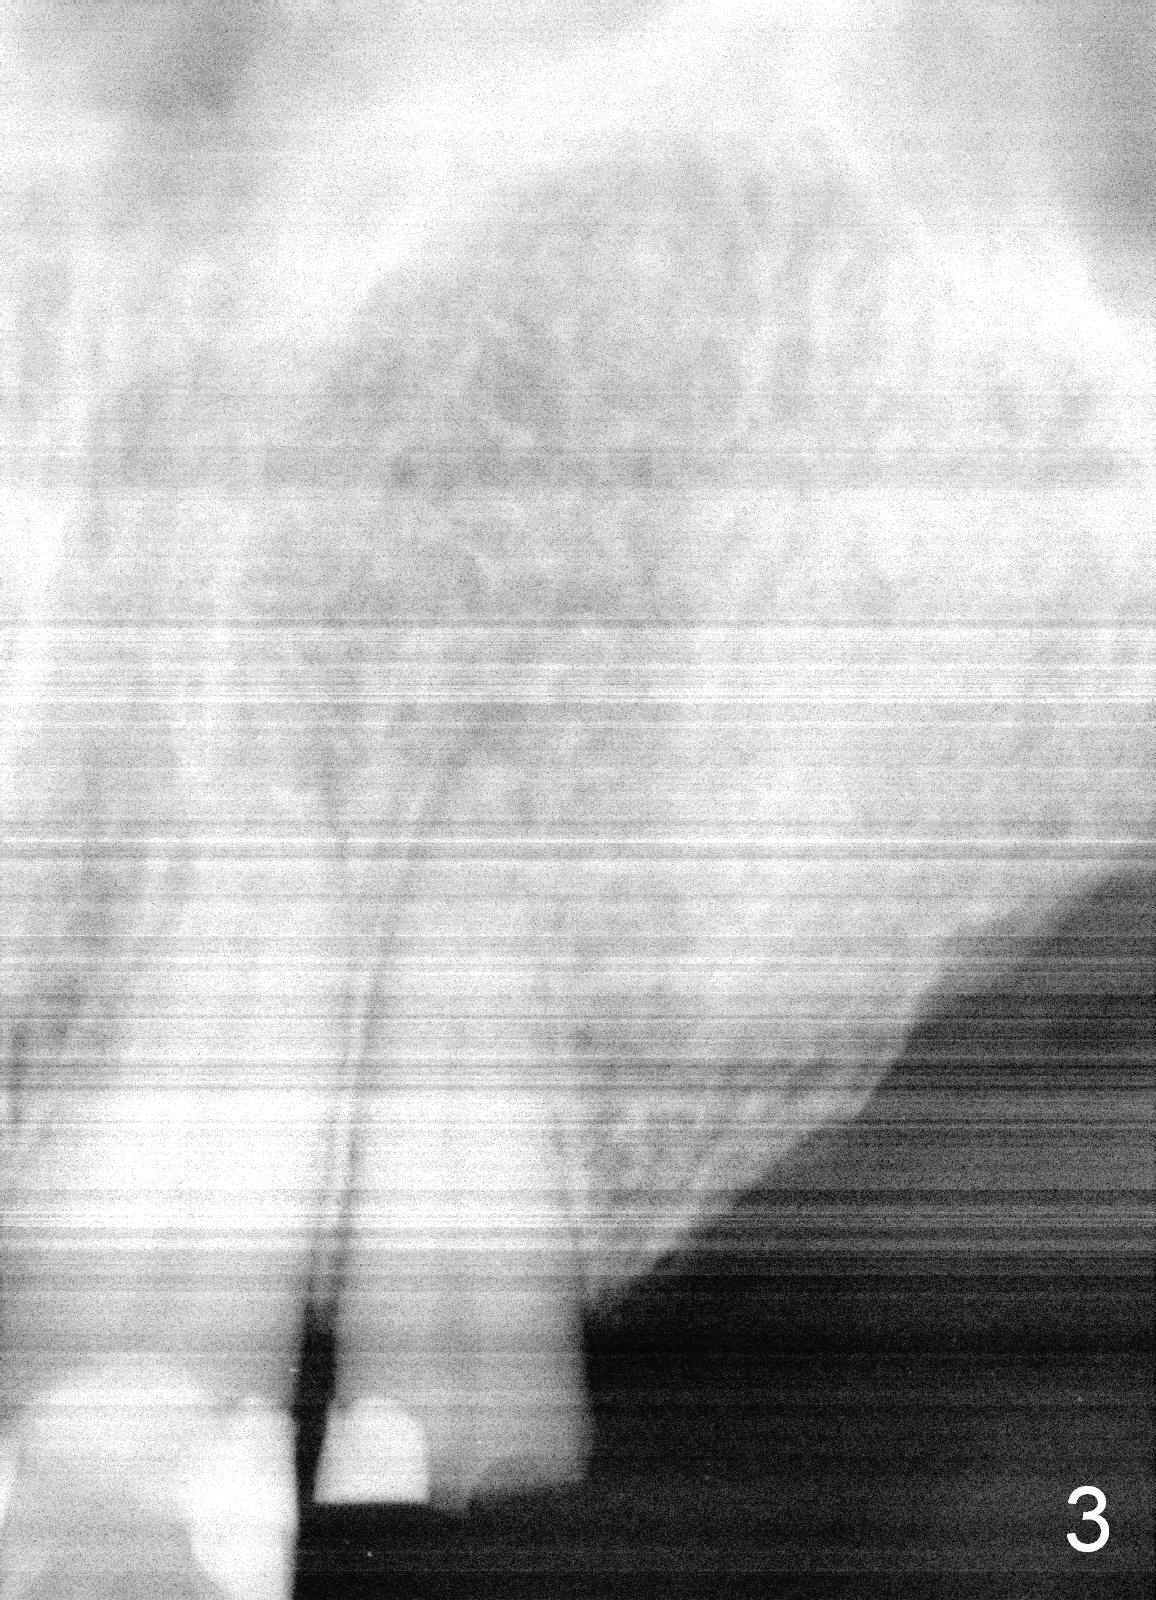

A 70-year-old man (TF) requests implant restoration for the upper left quadrant first (Fig.1), exactly #10 and 11 first (Fig.2-4). There is periapical radiolucency associated with the residual root at #10 (Fig.2 *). Local antibiotic will be Metronidazole. The root of #10 is long and large. The bone at #11 looks loose. Long implants will be placed (Fig.4). Osteotomy preparation should be less.

When initial osteotomy is established at #10 with insertion of a parallel pin, use 4.5 mm implant spacer to determine the initial point for #11 implant site (Fig.4: 6.49 (red line)-2=4.49 mm). 70岁男多个牙齿缺失,5.5年前就诊,同意在10-13位点植牙(图一)。